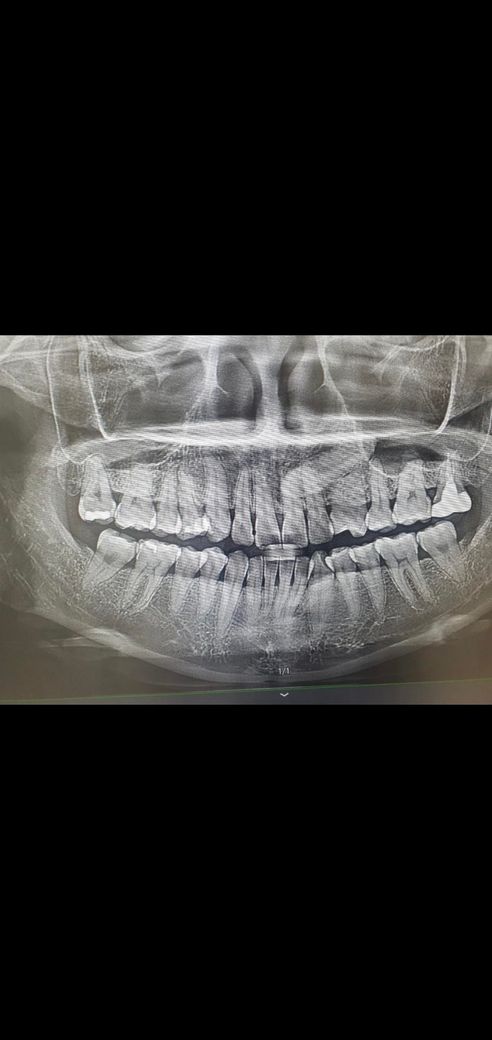

송곳니모양과 윗이빨과 안닿을때의 장단점

원래 이런모양일까요? 지금보니까 윗이빨안쪽에 있어서 몰랐는데 송곳니가 안쪽에 안닿더라고요 원래닿았던거 같은데

일부러안닿게 삭제를하면 좋은건가요..? 반대쪽도 두개 삭제되어있어요...

만약 안 닿는걸로 교합문제가 생기는거면, 이송곳니위만 닿게 떼우는 방법으로 해결이 될까요?

인레이 후 뭔가 턱이 불편해져서 이빤관찰하다 알았어요.

사진으로 보이는 부분은 정상적인 치아의 형태로 보입니다.

송곳니의 경우는 약간 뾰족하게 생기지만 사용을 하다보면 치아가 마모되서 닳아지는 경우도 있습니다. 일부로 치아를 삭제하실필요는 없습니다.

1. 인레이 후 교합이 달라졌다고 느껴진다면 인레이 보철물 교합조정을 받아야합니다

2. 그대로 두면 전체 교합균형에 안 좋습니다

3. 견치유도교합이 안되면 어금니 마모가 가속화됩니다